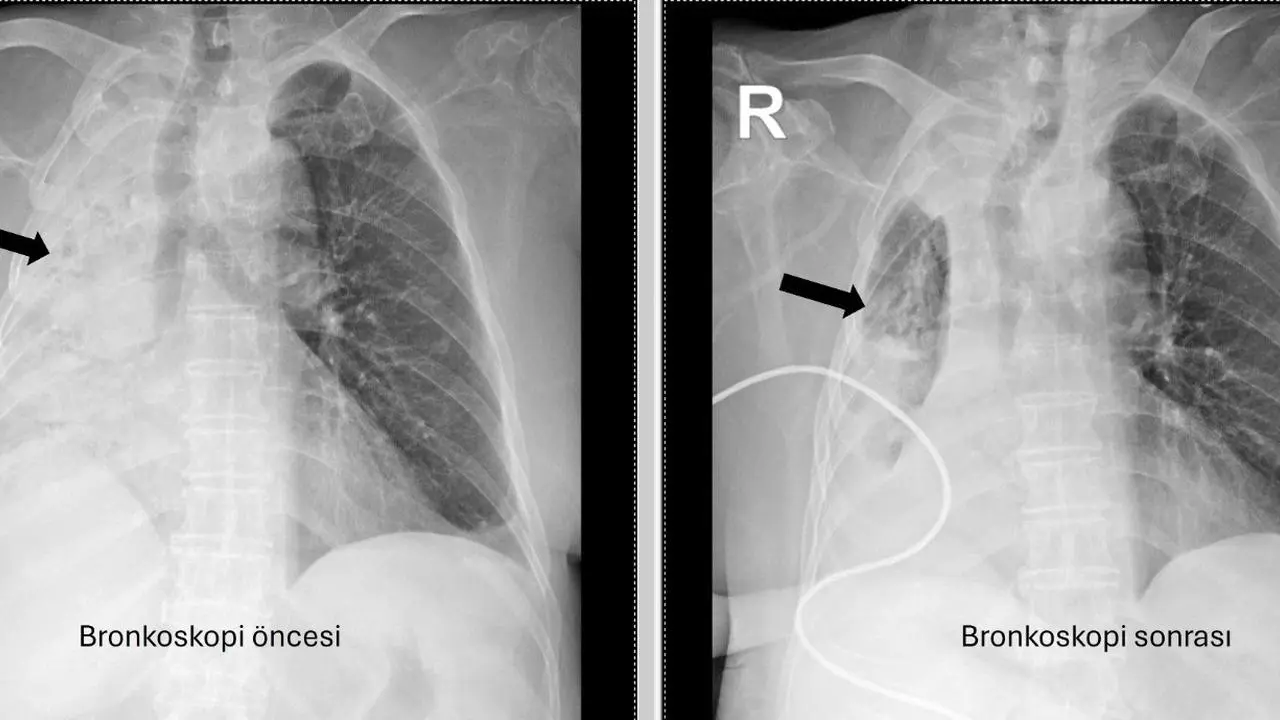

Denizli’de yaşayan 78 yaşındaki kadın, sık sık akciğer enfeksiyonu nedeniyle hastaneye başvurdu. Yapılan incelemelerde sağ akciğerinin tamamen kapalı olduğu anlaşıldı.

Bronkoskopi ile mısır tanesi bulundu

Pamukkale Üniversitesi Hastanesi’nde yapılan bronkoskopi sırasında hava yolunda sarı bir nesne tespit edildi. Bu nesnenin mısır tanesi olduğu belirlendi ve çıkarıldı.